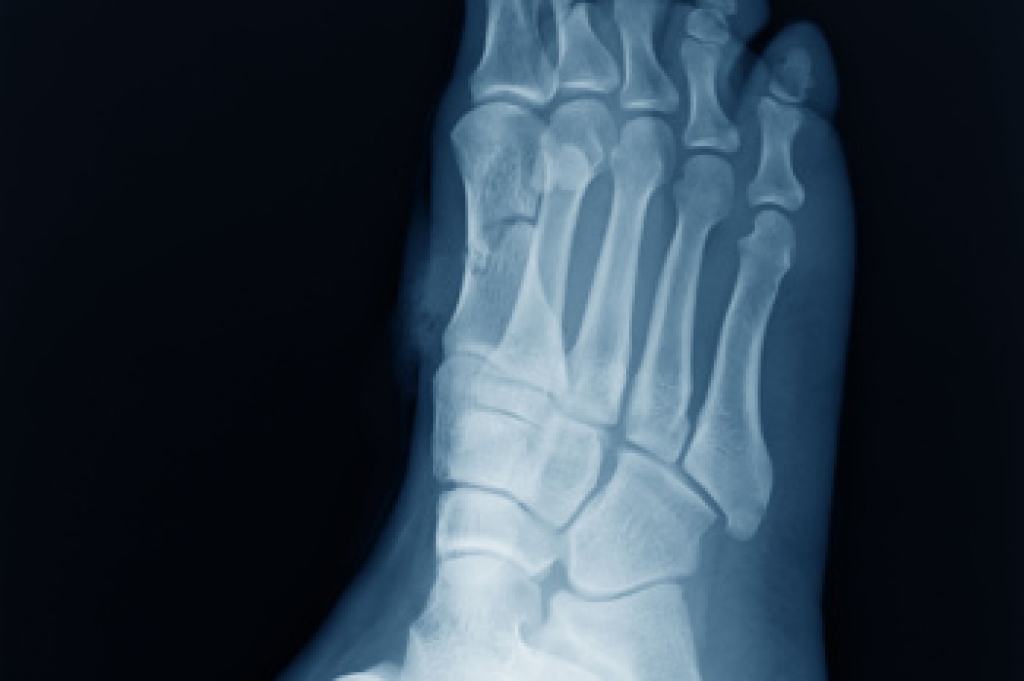

- Stress fractures can occur from overtraining, lack of calcium, or even your running style.